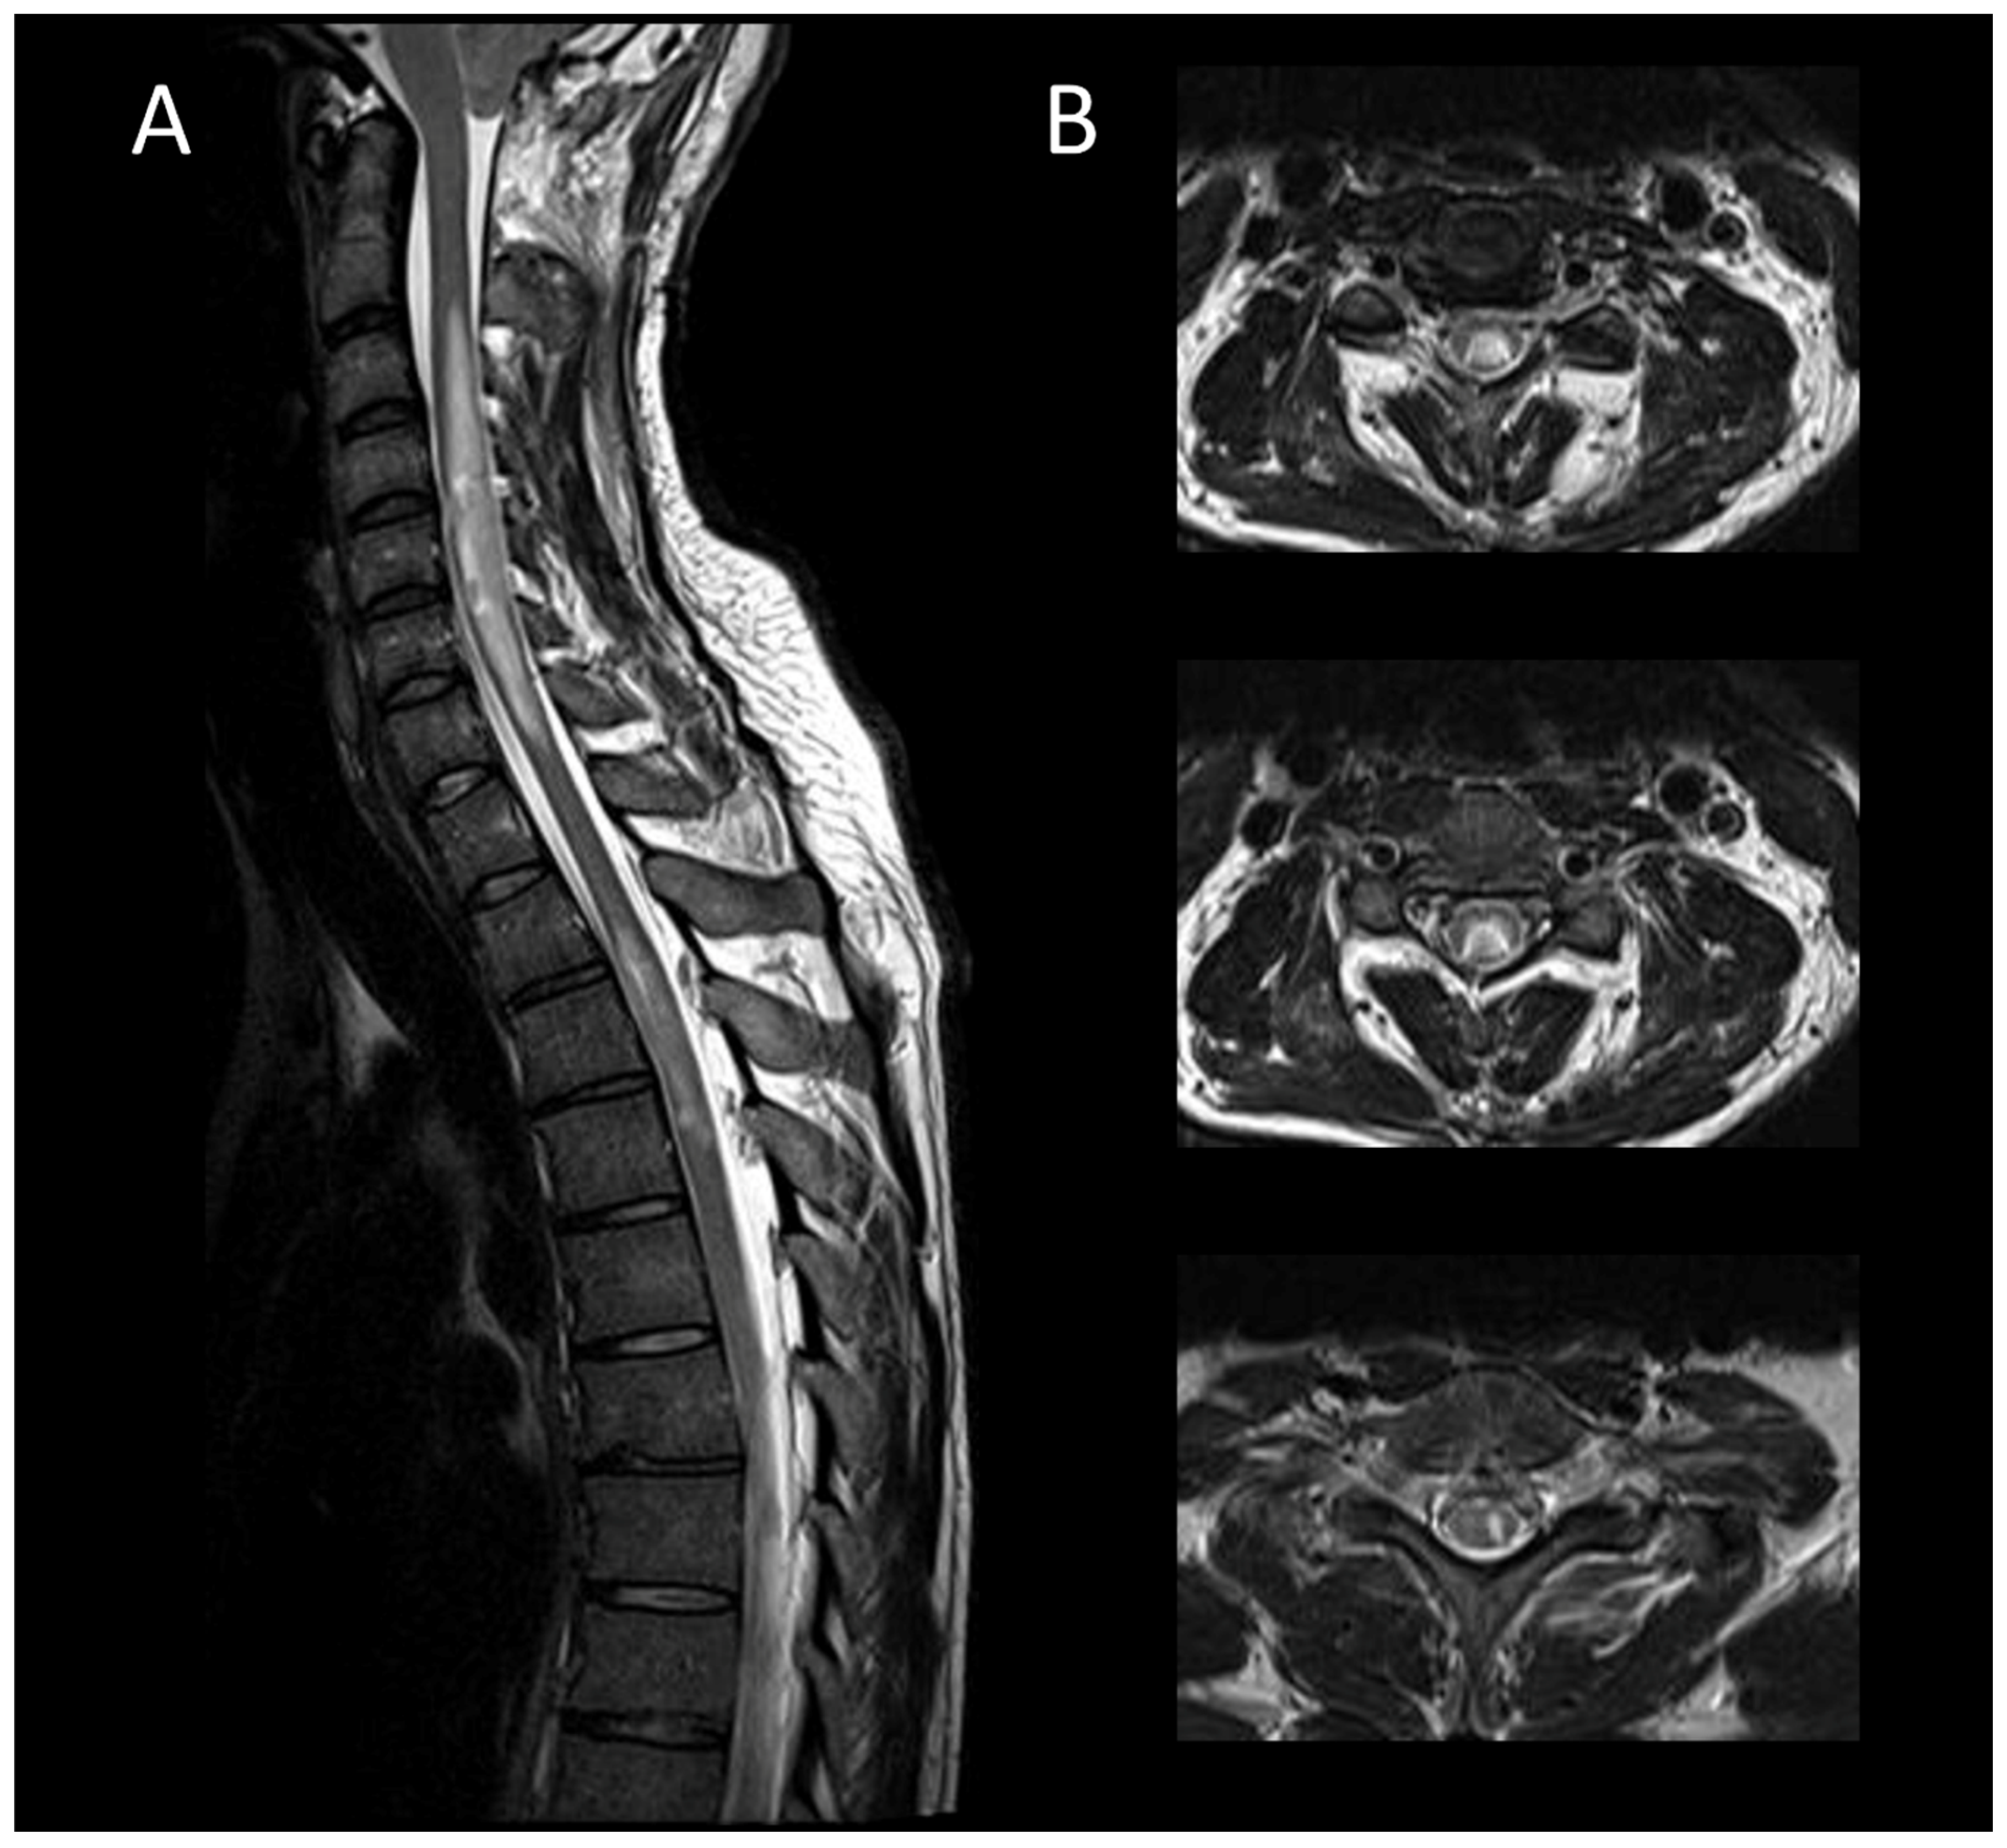

3.3.2. Spinal Dural Arteriovenous Fistula

3.3.3. Spinal Cavernous Malformation